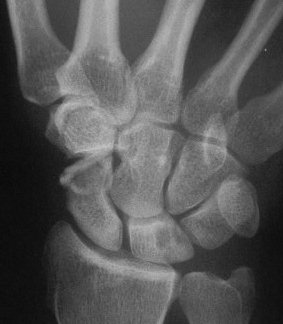

Clinically and by bone scan, this patient sustained a scaphoid fracture, but obviously had a preexisting distal pole cyst.

Intraoperatively, the distal pole cyst was eggshell thin with comminution into the ST joint. Stable fixation was not possible, even with a radial

styloid bone graft, and the distal pole was excised. Postoperatively, carpal instability was present.